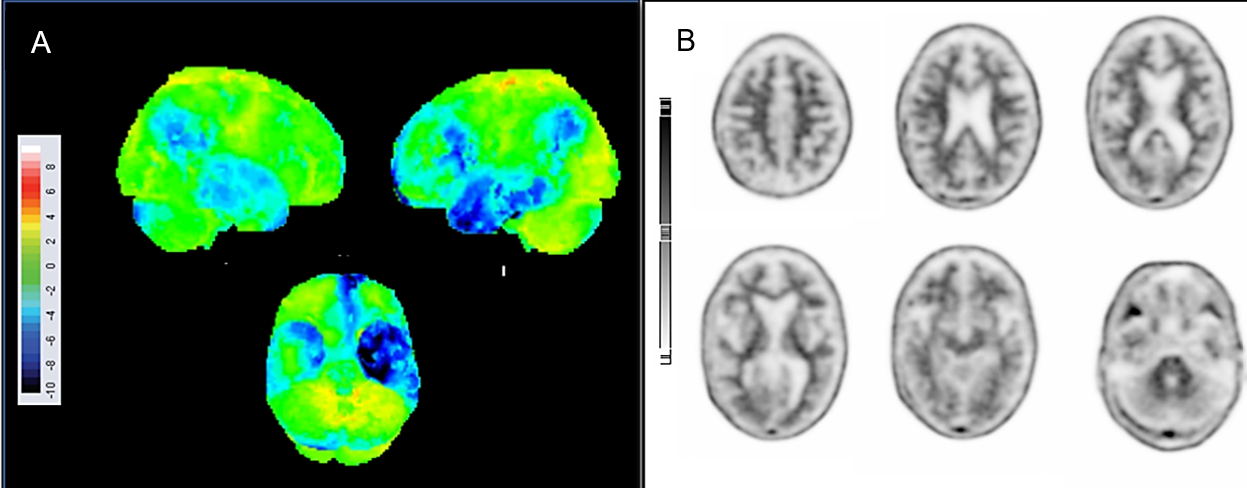

Results: A 78-year-old man presented with a six-year history of progressive memory decline, initially marked by difficulty with recent memory and mild anomia, evolving into motor clumsiness, gait impairment, language difficulties, and behavioural changes. Asymmetric parkinsonism emerged in later stages. Brain imaging revealed left temporal lobe atrophy and frontotemporal hypometabolism, with a negative amyloid PET, leading to a diagnosis of frontotemporal dementia [Figure 1 and 2]. Genetic analysis by exome sequencing revealed a mutation in the SQSTM1 gene (c.1210A>G; p. (Met404Val). Post-mortem brain autopsy confirmed frontotemporal lobar degeneration with atypical TDP-43 protein distribution, along coexisting with tau and Lewy body pathology [Figure 3].

Figure 2. [18F]-FDG PET and amyloid PET images.